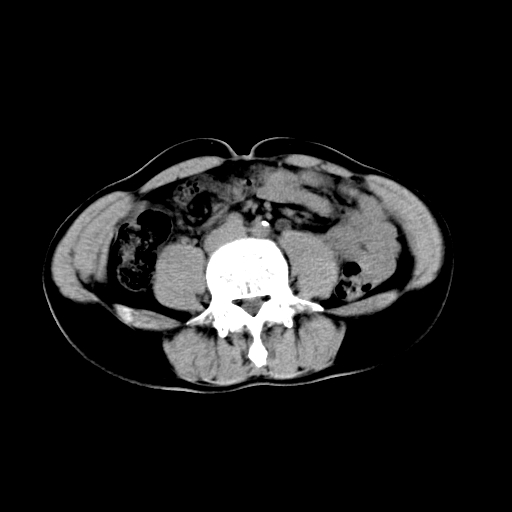

男,47岁,左输尿管结石碎石治疗后10余日。彩超示:左输尿管下段狭窄、输尿管积水。请各位讨论一下左输尿管下段结石还是静脉石?

两侧髂总动脉壁斑状及点状钙化.左侧输尿管行经与左髂总动脉相交后见高密度影,且下段输尿管管腔未见扩张,应该要考虑结石伴以上输尿管及肾盂积水.但右侧结节状高密度影,也应该是结石吧!那以上输尿管未见扩张呢!因此静脉结石可能性也较大.请问楼主碎石前左侧输尿管结石位置.

虽左侧有轻度肾盂积水但不支持结石。1结石边周应该有软组织包绕呈晕征。2钙化点前面见输尿管影也不支持是结石。3彩超没提结石。建议超生复查。

输尿管先位于腹部,后进入盆腔,最后斜穿膀胱壁开口于膀胱,因此,临床上常将输尿管分为腹段、盆段和壁内段。第1个狭窄:在肾盂与输尿管移行处。第2个狭窄:在跨过髂血管处。第3个狭窄:在穿过膀胱壁处。这些狭窄是结石容易滞留的部位。

左侧输尿管有轻度扩张伴有肾盂积水,输尿管下段周围的高密度影不象在输尿管内。

同意,不支持结石。(因显示该高密度影前见扩张输尿管影,另外两侧对称显示)。

左侧高密度影在左侧输尿管的内侧方,所以不考虑输尿管结石.

我认为不是结石的可能性大,因为他的位置和血管钙化的位置邻近